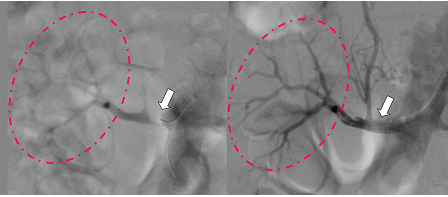

図の説明

左 矢印の部分の血管が狭窄しています。ピンクの点線部内の血流ははっきりしません。

右 ステントを留置して血流が改善しました(矢印)。ピンクの点線部内の血流が良く分かります。